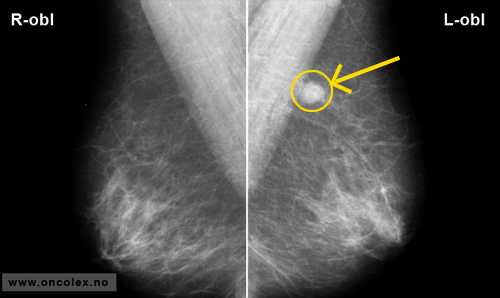

Eksempler på mammografibilder

Mammografi horisontalt plan (frontprojeksjon) av begge bryst. Suspekt fortetning i venstre bryst.

Mammografi vertikalt plan (skråprojeksjon) av begge bryst. Suspekt fortetning i venstre bryst.